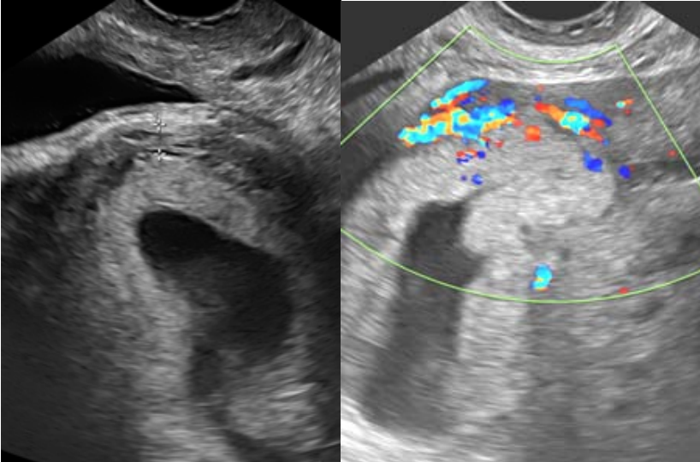

Paciente, 31 anos, tercigesta (duas cesarianas anteriores), na 7ª semana de gravidez com queixa de sangramento genital há 15 dias, com piora há 24 horas. Ao exame, encontrava-se com estado geral bom, hipocorada (+/4+), acianótica, consciente e orientada. Pressão arterial de 120 x 80 mmHg. Frequência cardíaca de 88 bpm. Abdome plano depressível e indolor, sem massas palpáveis e ausência de sinais de irritação peritoneal. Submetida a exame ultrassonográfico transvaginal, com a imagem abaixo revelando saco gestacional dentro de cavidade uterina, de contorno regular, em topografia de istmocele.